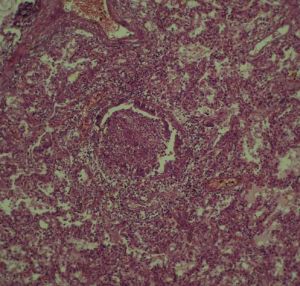

暴發性肝衰竭值得注意的是在暴發性肝衰竭患者肝臟壞死區的分布和各肝葉壞死程度呈極顯著的非均質性,在不同部位肝穿刺活檢的結果可以完全不同,因此肝穿刺活檢對確診和判斷預後的價值是有限的;臨床表現相同的暴發性肝衰竭其肝臟組織病理表現可完全不同;殘留的肝細胞的多少可能並不能決定存活率的高低;另外暴發性肝衰竭也可發生於肝硬化的基礎上。